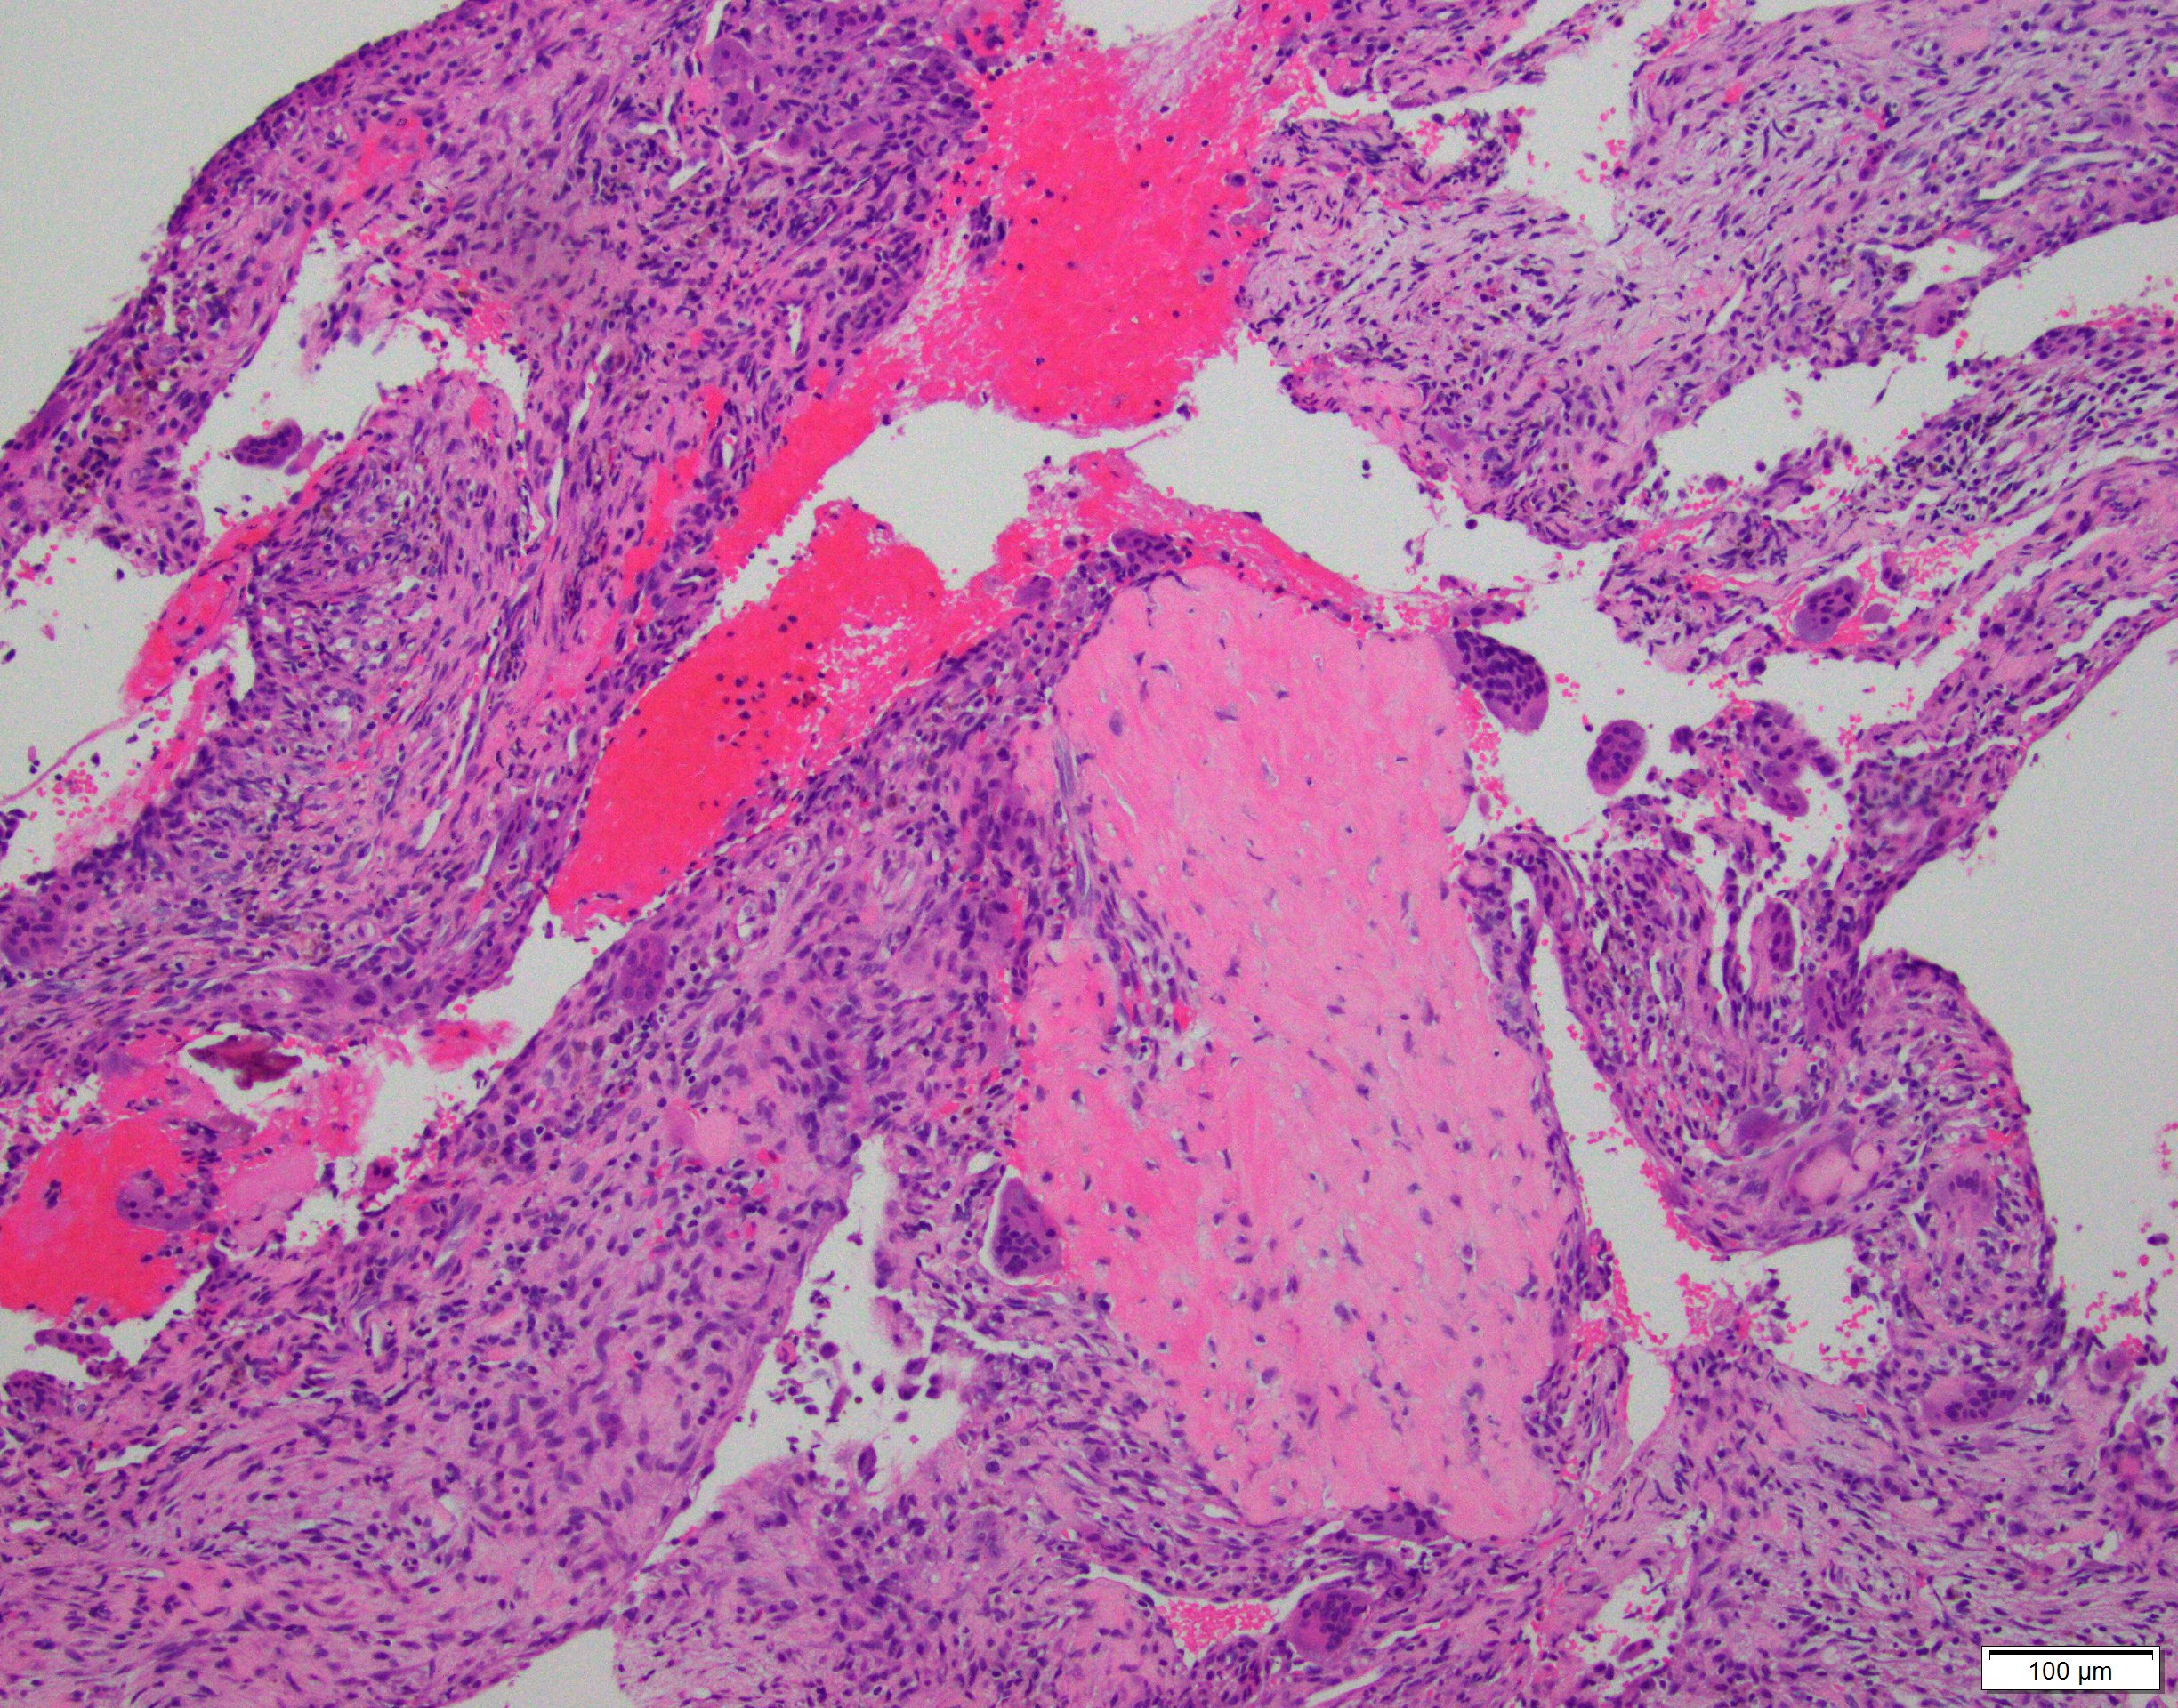

- Multiloculated cystic lesion

- Blood filled cystic spaces separated by cellular septa containing fibroblasts, giant cells and woven bone

- Calcified, basophilic material (blue reticulated chondroid-like material)

- Necrosis not common but mitotic activity is easily identified

- No cytologic atypia (Am J Clin Pathol 2015;143:823)

- Numerous giant cells in connective tissue that line large sinusoidal spaces

Microscopic (histologic) images

Contributed by Elham Nasri, M.D. and Kelly Magliocca, D.D.S., M.P.H.

A. Aneurysmal bone cyst. The H&E shows cystic spaces with stromal giant cells. Rearrangement of USP6 gene confirms the diagnosis in the above clinical and radiographic context.